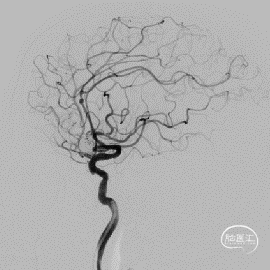

术前DSA的正位、侧位造影:

右侧颈内动脉DSA:

术后即刻正侧位造影显示:小阜及瘤体致密栓塞,支架贴壁和导流良好。